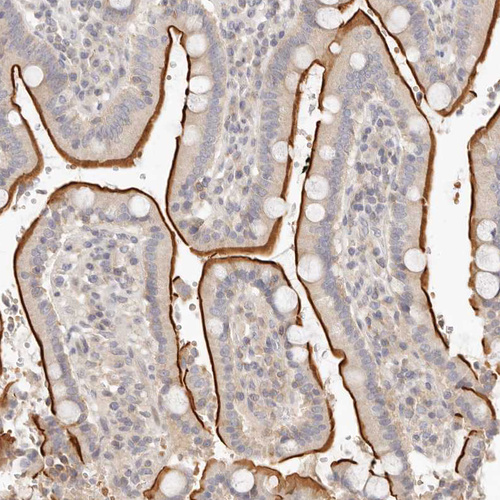

HPA029680

leukotriene B4 receptor 2

Anti-LTB4R2 Antibody

Polyclonal Antibody against HUMAN LTB4R2